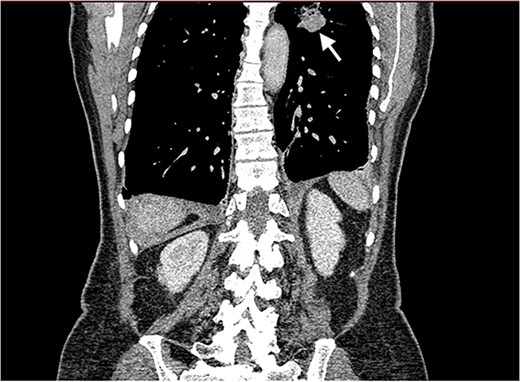

Echocardiography revealed a 1.2 cm pedunculated mass attached to the anterior mitral valve leaflet (AMVL) with severe mitral regurgitation (Fig. 1). Computed tomography imaging revealed multiple hepatic lesions (suspected septic emboli, Fig. 2), and a cavitating mass in the posterior aspect of the left upper lobe of the lung (Figs 3 and 4). Magnetic resonance imaging showed multiple cerebral lesions (Fig. 5), also thought to be septic emboli. Her presentation was suspected to be due to infective endocarditis rather than ischaemic, as troponin was negative, and coronary angiography was unremarkable. She was therefore treated promptly with intravenous vancomycin and gentamicin as per local antimicrobial guidelines. However, she failed to recover, and her case was reviewed in the regional in-house urgent cardiac surgical multidisciplinary team meeting. Considering her persistent fever, as well as the recurrent emboli, the decision was made to transfer her to our centre for emergency surgery.

Coronal CT image of the lungs showing the cavitating mass suspected to be an abscess.